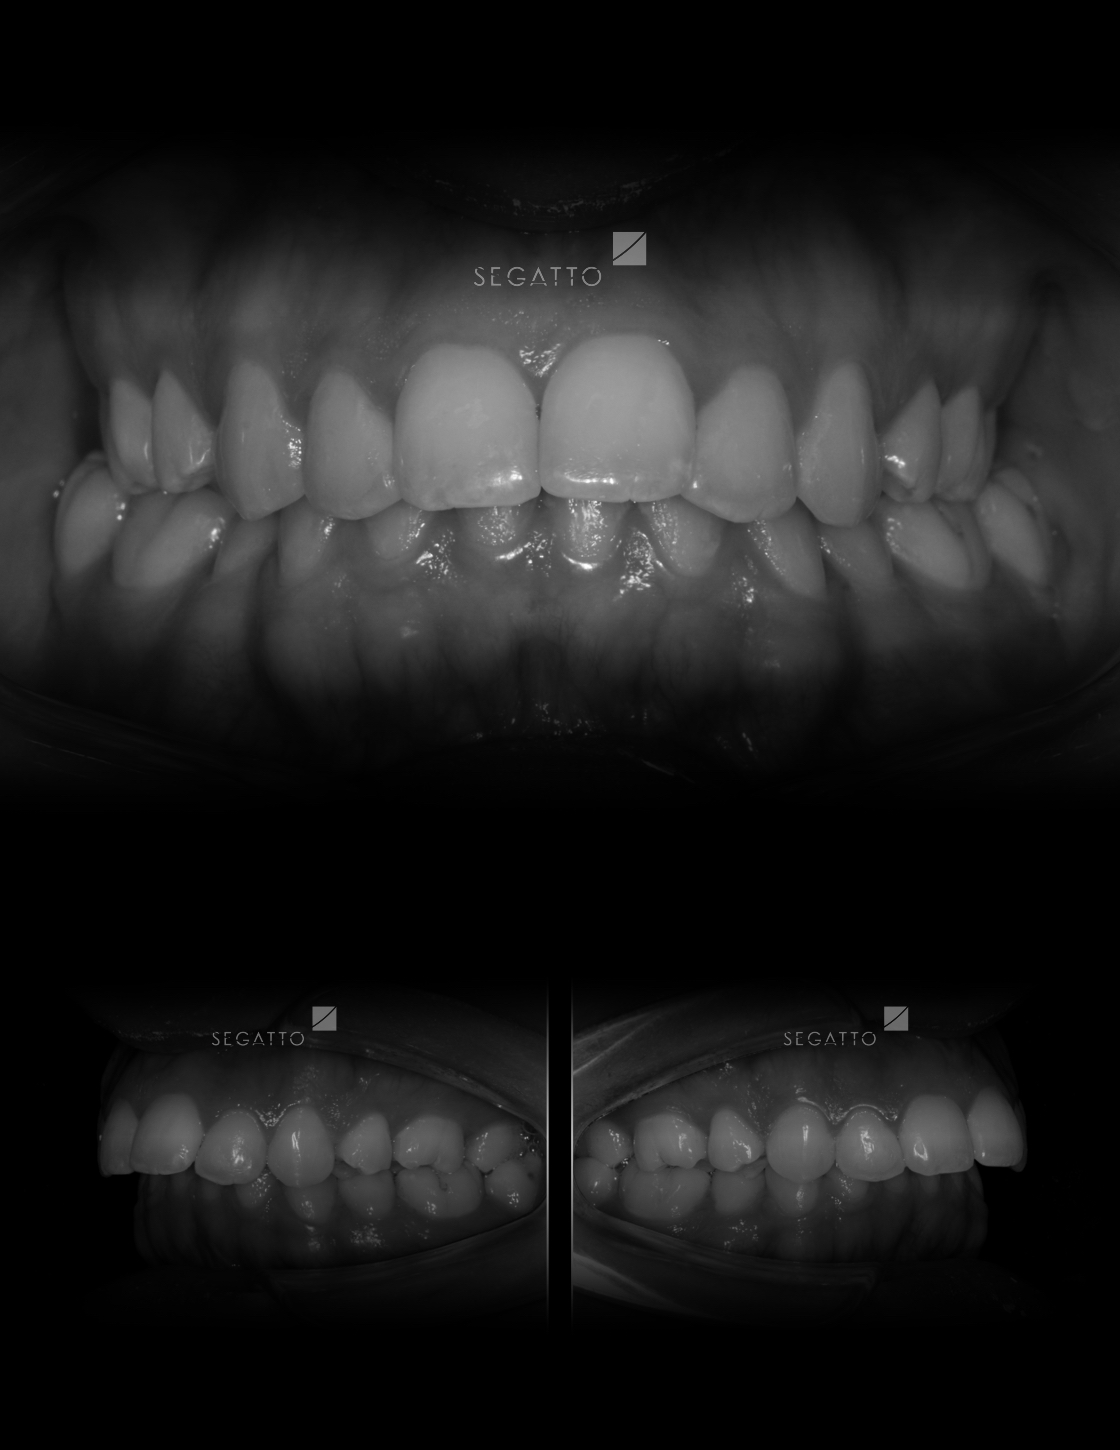

Orthodontics

Cases